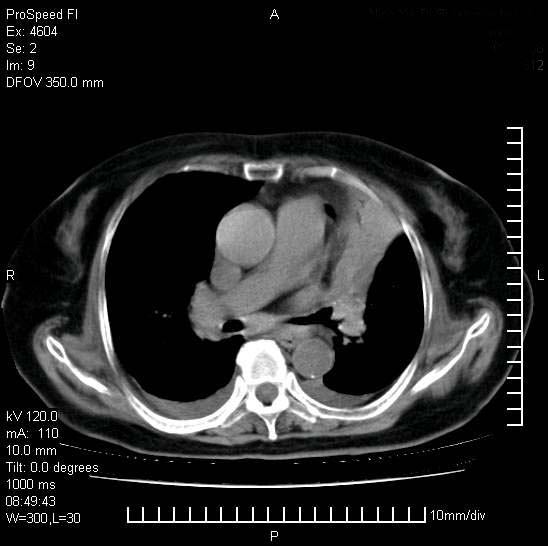

十几年前曾患肺结核,一周前突咳血约100ml,中性粒细胞稍高,诊断两上肺陈旧结核,下肺炎症,给予抗炎治疗,近几日晚上高热,39度,仍咳少量血,4天前ct及今天ct上传。

[face=黑体]8月30日[/face]

支持陈旧性肺结核并两下肺感染,两侧胸腔积液。

短短几天内,病变范围明显增多扩大,以左侧明显,而且双侧出现胸水,还是考虑感染.

短短几天内,病变范围明显增多扩大,以左侧明显,而且双侧出现胸水,我更多考虑左侧中心性肺癌并并阻塞性不张及肺炎,炎症变化也太快了!

1)两肺结核并感染。2)不排除左肺上叶中央型肺癌并阻塞性肺炎、肺不张可能;建议行纤支镜检查。3)右肺门及纵隔淋巴结肿大。4)双侧胸腔积液。

陈旧性肺结核及左下肺不张,咯血后肺部感染,双胸腔积液,高热可能与痰液引流不畅有关。